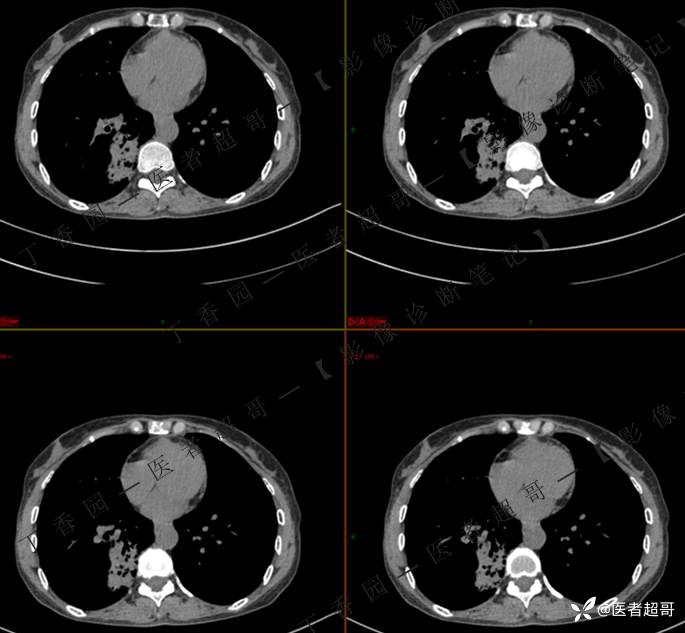

2402胸部影像病例︱持续追踪的一个患者,时间轴较长,闭卷分析,请畅所欲言~~~

女性,57岁

临床治疗一周后复查

第二次检查